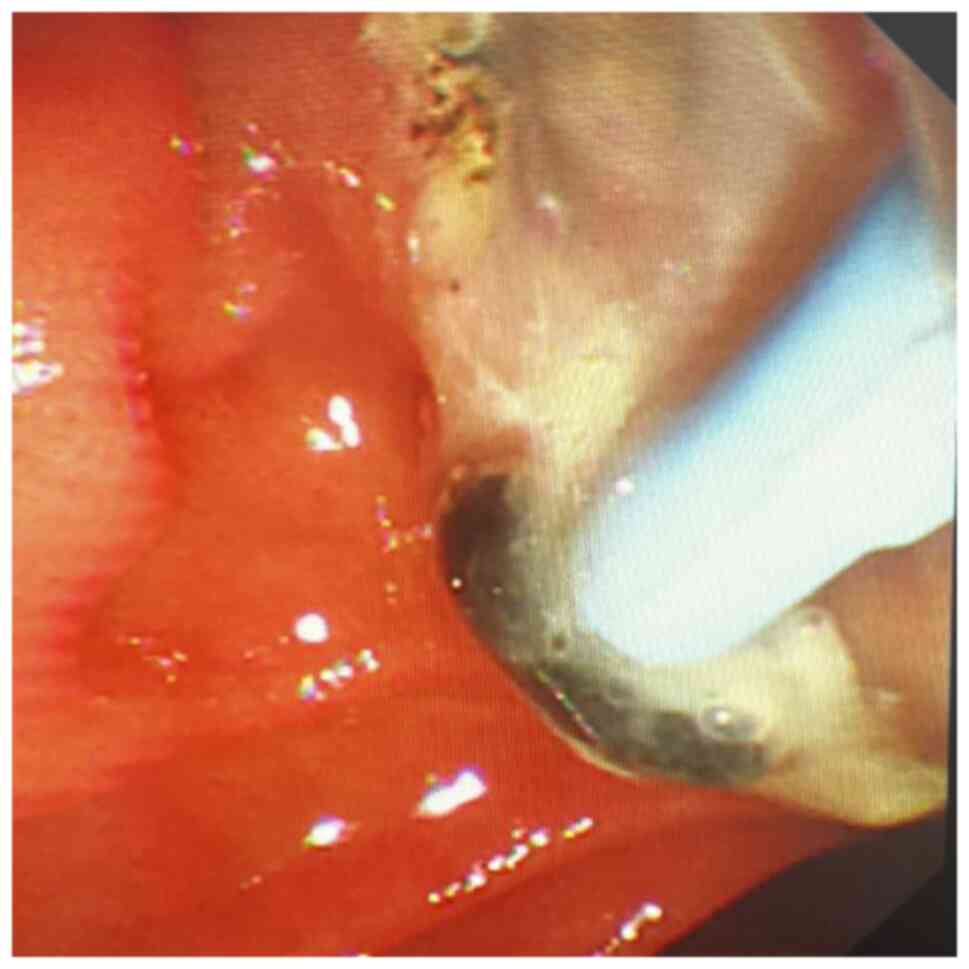

Charcot's triad, shock and central nervous system depression were observed in 14 of 47 patients with AOSC. A total of 33 patients were found to have between two and four features of Charcot's pentalogy, including one patient with coma. After having performed clinical and endoscopic minimally invasive treatments, purulent bile outflow was observed in 47 patients with AOSC (Figs. 1 and 2), including 41 cases of common bile duct stones (Figs. 3 and 4). The end-stage tumors included bile duct malignancy in four cases and pancreatic cancer in two cases and the clinical symptoms were significantly improved. In this group, on day 7 after endoscopic treatment, blood inflammatory indexes and liver function were found to be significantly improved the most of the group compared with the measured values at admission: The level of PCT decreased from 8.95±15.26 to 0.42±0.37 ng/ml, the level of CA-199 was reduced from 635.04±907.76 to 164.68±475.78 kU/l and that of ALT was decreased from 190.96±105.91 to 50.56±20.33 µmol/l. The value of the direct bilirubin test was decreased from 62.21±36.23 to 30.64±15.40 µmol/l and these differences were found to be statistically significant (P<0.05 or P<0.01), as shown in Table VII. Out of the total of 47 patients, 16 cases involved the use of ERCP and ENBD, 17 cases included the use of ERCP, EST and ENBD, 14 cases included the use of ERCP and ERBD, and 28 cases included the use of ERCP for stone extraction. During ERCP examination, purulent bile was discharged from the bile duct. A total of three patients underwent secondary ERCP (Table VI). Out of the total cases, 35 (74.5%) showed positive results in the bile culture. The predominant bacterium species identified were Gram-negative bacteria, with Escherichia coli being the most frequently observed in 11 instances (31.4%). Klebsiella pneumoniae was detected in seven instances, accounting for 20% of the cases. Pseudomonas faecium was identified in five cases (14.3%), Enterococcus faecium in four cases (11.4%), Pseudomonas aeruginosa in four cases (11.4%), Staphylococcus aureus in three cases (8.6%) and Enterococcus casselifavus in two cases (5.7%). There was one case of both E. faecium and E. coli (2.9%), two cases of K. pneumoniae and Candida albicans (5.7%), one case of E. faecalis, K. pneumoniae and Enterococcus casselifavus (2.9%), one case of Aeromonas hydrophila (strain found in guinea pigs) and E. faecalis (2.9%), and two cases of E. faecalis and E. coli (5.7%). There were two cases of Citrobacter freundii and Stenotrophomonas maltophilia, accounting for 5.7% of the cases. Additionally, there was one case of E. faecium and C. albicans, which made up 2.9% of the cases. Within 1 to 7 days after treatment, the high fever of 45 of the patients disappeared and their body temperature returned to normal. It was difficult to completely control the infection in the remaining two patients after 7 days of ERCP treatment. One of these patients was an elderly patient (≥80 years old) with a secondary tumor and stenosis of bilioenteric anastomosis complicated with AOSC. Even though the infection was not entirely treated while the patient was in the hospital, the family members requested that the patient be discharged. Another patient with multiple common bile duct stones complicated with sepsis underwent some improvements after a second line of ERCP was performed and was discharged. Within 7 days of treatment, the abdominal pain of 27 patients, and jaundice experienced by 29 patients, were resolved. Hyperamylasemia or acute pancreatitis (mild) occurred in three patients following ERCP, which itself improved after conservative treatments. The average hospital stay per patient was 11.9±4.6 days. Finally, no severe complications, including perforation, bleeding, severe pancreatitis or mortality, were identified for any of the patients.

Figure 1

Purulent bile and black bile duct stones.